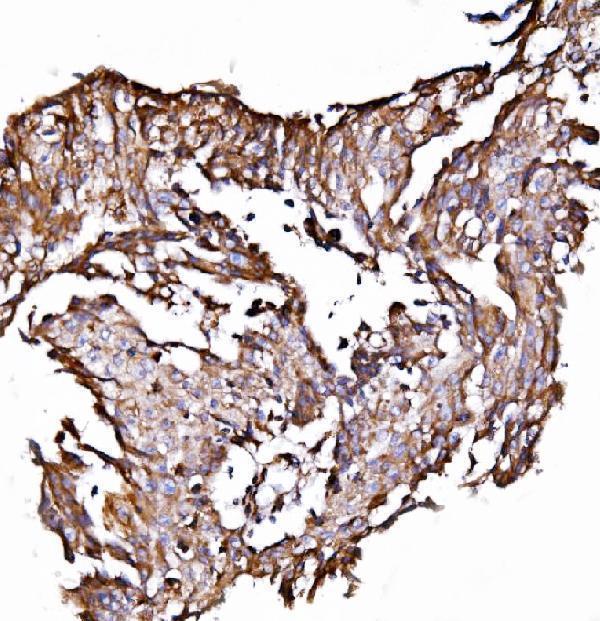

IHC analysis of ORP150/HYOU1 using anti-ORP150/HYOU1 antibody (A04934-2).

ORP150/HYOU1 was detected in a paraffin-embedded section of human laryngeal squamous cell carcinoma tissue. Heat mediated antigen retrieval was performed in EDTA buffer (pH 8.0, epitope retrieval solution). The tissue section was blocked with 10% goat serum. The tissue section was then incubated with 2 μg/ml rabbit anti-ORP150/HYOU1 Antibody (A04934-2) overnight at 4°C. Biotinylated goat anti-rabbit IgG was used as secondary antibody and incubated for 30 minutes at 37°C. The tissue section was developed using Strepavidin-Biotin-Complex (SABC) (Catalog # SA1022) with DAB as the chromogen.